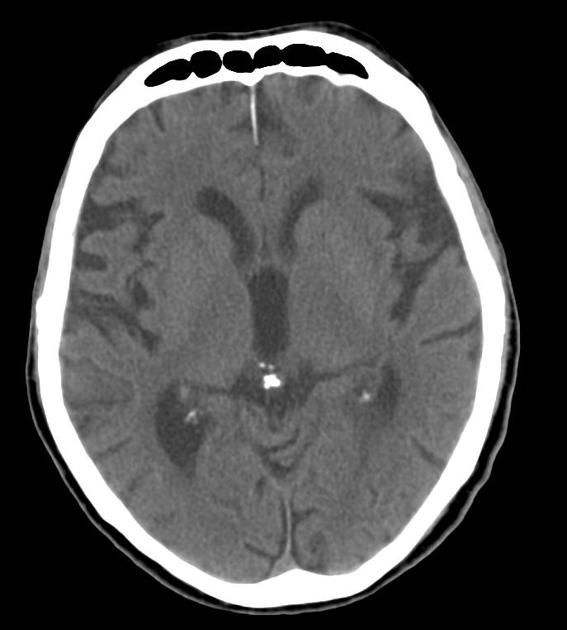

Brain sand also known as corpora arenacea is a benign calcification that is present in the pineal gland and in other structures of the brain such as choroid plexus. The concentration of brain sand tends to increase with age resulting in enhanced visualisation of the pineal gland on X-ray overtime (usually by third to fourth decade). Clinically, these calcification are helpful as anatomical landmarks in radiological examinations. Text Reference: https://en.wikipedia.org/wiki/Corpora_arenacea Image Source: https://radiopaedia.org/cases/pineal-gland-calcification